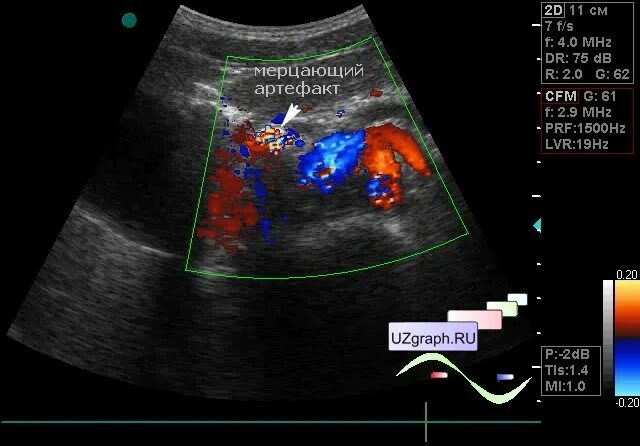

Что такое при цдк